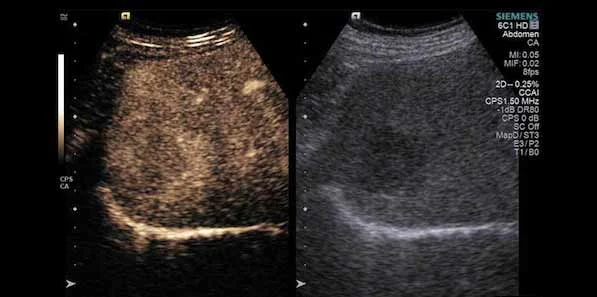

Siemens’ HELX platform offers an ergonomically-designed control panel and adjustable monitor for heads-up, no look operation of the system. Further helping to streamline workflow, the HELX also offers two redesigned women’s health transducers for enhanced patient comfort and improved clinician access. Powered by the new SieStream™ HD architecture, the HELX also boosts image quality with a large 21.5 inch LCD monitor, HD transducers, contrast agent imaging technologies and powerful image processing.

“The image quality offered by Siemens’ ACUSON S1000TM ultrasound system is great and the multimodality review mode, that offers the ability to bring relevant MR images up on one screen at the same time when looking for something tiny in the breast, is a huge benefit to us,” adds Alison Darlington. “The system’s MMR facility was a key factor for us during the selection process, with the hockey stick probe, in particular, making looking at the areola easier.”